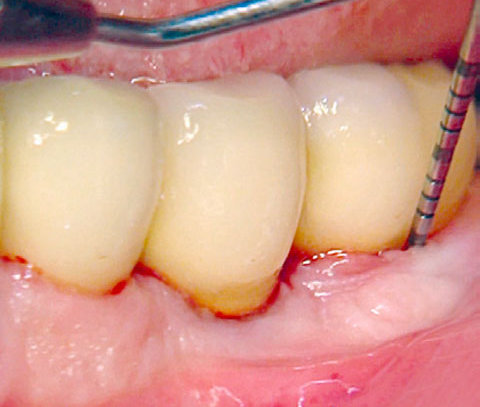

Mechanische Reinigung mit und ohne PERISOLV®

* Fördert bei der mechanischen Reinigung die Entfernung der Bakterien.